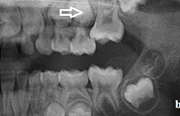

Esimeste molaaride (purihammaste) lõikumine. 1. molaaride ektoopilise lõikumise jälgimine. Ülemised ja alumised esimesed purihambad e. molaarid lõikuvad orienteeruvalt6-7-aastaselt piimahammaste rea lõppu. Enamasti lõikuvad samanimelised jäävhambad paaridena. Normaalne lõikumise Loe edasi »